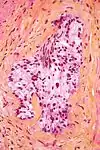

Micrograph demonstrating perineural invasion. HPS stain.

In pathology, perineural invasion, abbreviated PNI, refers to the invasion of cancer to the space surrounding a nerve. It is common in head and neck cancer, prostate cancer and colorectal cancer.